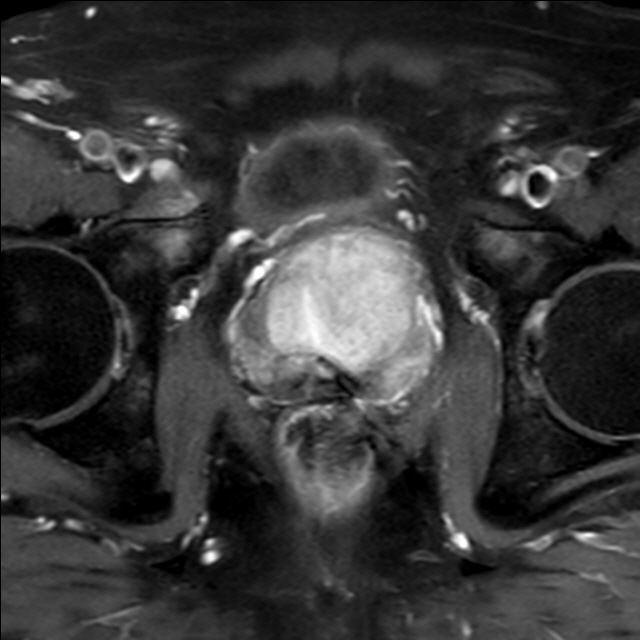

Prostata (mpMRT)

Die multiparametrische MRT der Prostata (mpMRT) bietet eine gute Möglichkeit, mittels bildgebender Diagnostik die Lokalisation, die Ausdehnung und eventuelle Aussaat eines Prostata-Karzinoms darzustellen. Die Untersuchung dient meist der Abklärung unklarer Tastbefunde, Ultraschallbefunde oder wiederholt erhöhter oder steigender PSA-Werte in der Labordiagnostik.

Die bildgebende Diagnostik der ersten Wahl ist zwar der Ultraschall mit einer Spezialsonde beim Urologen und ggf. die ultraschallgesteuerte Stanzbiopsie verdächtiger Befunde. Bei fehlender Darstellung des Tumors im Ultraschall oder vergeblichen Biopsien kann aber die MRT als Problemlöser eingesetzt werden: Sie zeigt dem Urologen, wo eine weitere Biopsie die Diagnose sichern kann. Außerdem kann die MRT bei ausgedehnten Tumoren einen Überblick über die Beteiligung der Nachbarorgane verschaffen und Absiedlungen (Metastasen) entdecken.